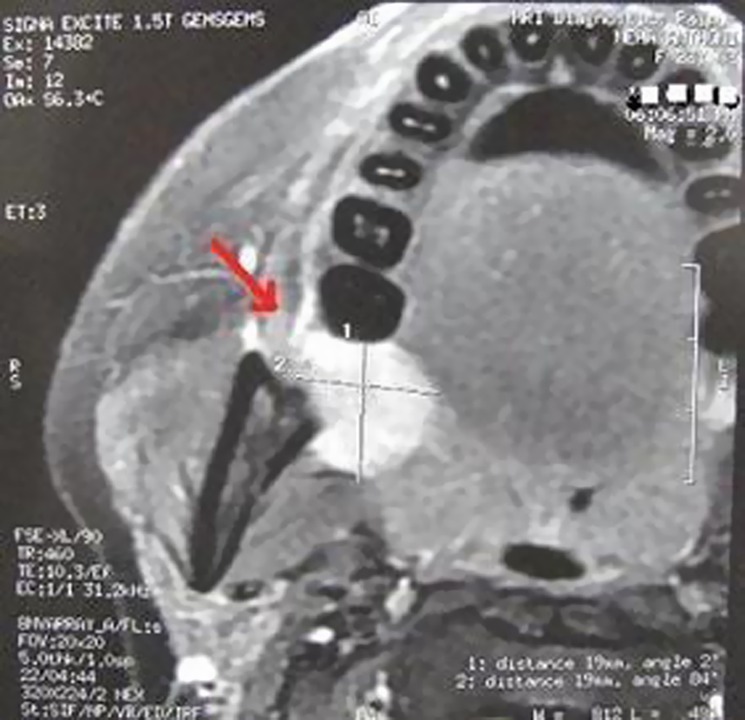

Magnetic resonance imaging (MRI) revealed a mass with a clear and smooth border in retro molar region measuring about 19 × 19 mm2, there was no obvious abnormalities of surrounding soft tissues (Fig. 2).

Fig. 2.

Magnetic imaging resonance reveals well define mass measuring 19 × 19 mm2